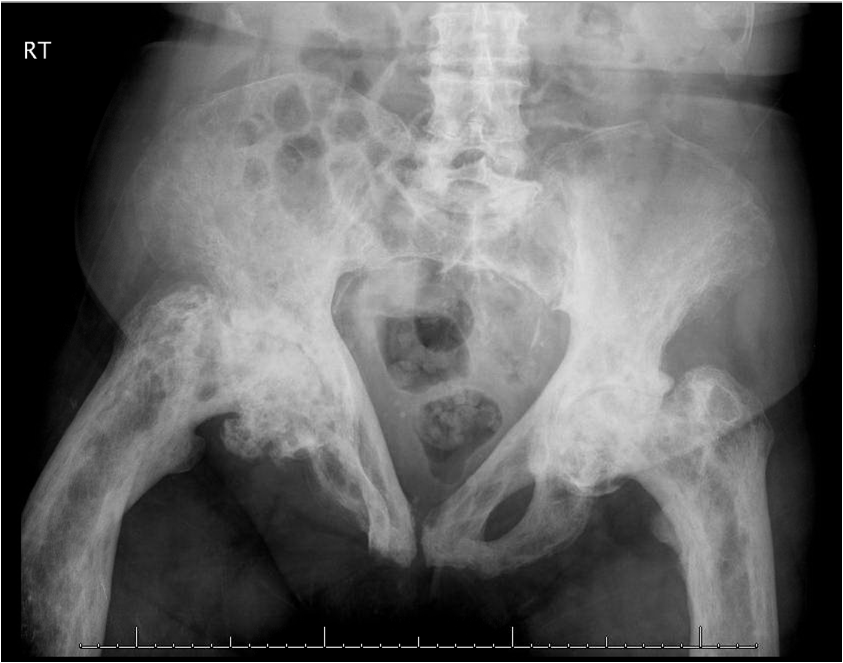

Oral etidronate, IV pamidronate, and then zoledronate caused bone markers to normalize in this 80-year-old woman-temporarily. What’s going on? Answer this and questions on 3 other topics in this week’s quiz.

The correct answer is d. Paget disease of bone.